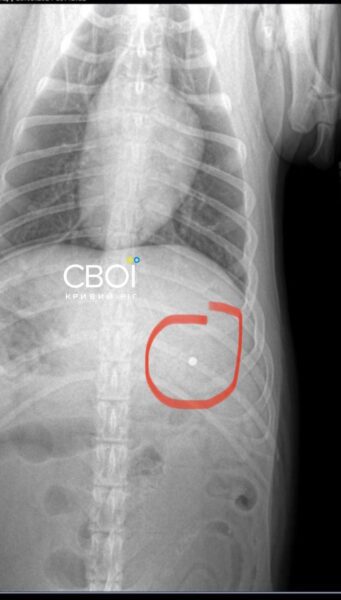

Ветеринар призначив лікування для Баті. Одна з куль застрягла у голові тварини, інша – біля шлунка. Дістати їх, аби не нашкодити собаці, неможливо.